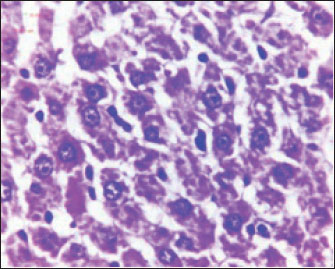

The histopathological results in the TCE group showed that the treatment with TCE for 90 days ( 110 LD50daily) resulted in the infiltration of inflammatory cells, mainly lymphocytes, in portal area with mild fibrosis, hyperplasia of the bile duct (Fig. 3) showed congested central vein, proliferation of Kupffer cells, apoptotic cells and, with dilated sinusoids, while the (Fig. 4) showed severe fatty changes of hepatocytes in the form of cytoplasmic lipid droplets (microvascular steatosis) with proliferation of Kupffer cells. (Fig. 5) showed degenerative changes with necrosis of hepatocytes with proliferation also (Fig. 6). Histopathological section of the liver (group + with oil) showing mild degenerative changes of hepatocytes. In Fig. 7, the histopathological section of the liver (c +group/90 days) showing mild degenerative changes of hepatocytes with few inflammatory cells infiltration (Fig. 8). Finally, in Fig. 9, histological section of the liver (control group) with normal structure.

Fig. 5. Histopathological section of the liver (TCE group/90 days) showing severe fatty changes in hepatocytes in the form of cytoplasmic lipid droplets (microvascular steatosis) with proliferation of Kupffer cells (H&E stain 400X).